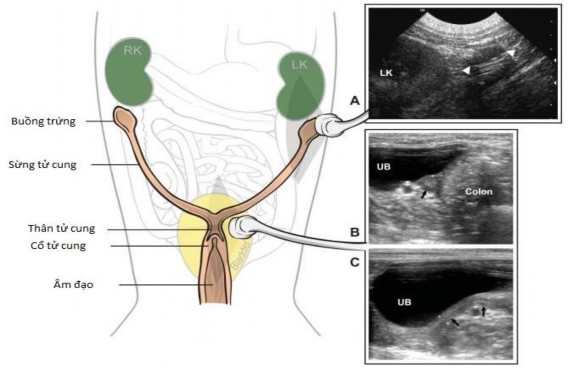

Hình 2.4. Đường sinh dục con cái bình thường, bên trái là một sơ đồ biểu diễn giải phẫu của đường sinh dục con cái

Chú thích: Buồng trứng nằm ở cuối và thường ở bên thận. Cổ tử cung và thân của tử cung được đặt trên mặt lưng bàng quang tiết niệu. Sừng tử cung được bộc lộ ra phía trước bên ngoài từ thân tử cung và có thể nhìn thấy không thường xuyên trong chu kì không động dục. A: Hình ảnh mặt cắt thẳng đứng dọc ở chính giữa của một buồng trứng bên trái bình thường (đầu mũi tên). Thận trái (LK) được sử dụng làm mốc và buồng trứng được xác định là một cấu trúc mô mềm hình trứng có độ vang trung bình đến đuôi của thận. B, C: Hình ảnh ngang (B) và mặt cắt thẳng đứng dọc ở chính giữa (C) của tử cung chó bình thường trong chu kì không động dục. Trên hình ảnh ngang, tử cung (mũi tên đen) được xác định là một cấu trúc vòng tròn giữa bàng quang (UB) và đại tràng, được sử dụng làm mốc. Trên hình ảnh mặt cắt thẳng đứng dọc ở chính giữa, tử cung (mũi tên đen) được xem như một cấu trúc hình ống có độ vang trung bình ở mặt lưng của bàng quang.

Nguồn: Rachel Pollard & Silke Hecht (2015)